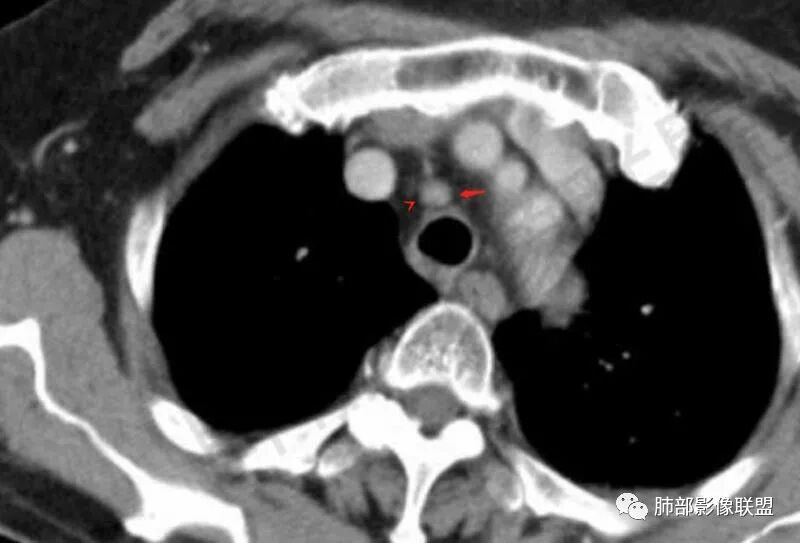

主支气管后缘外可见一实性结节,病变跨支气管管壁生长,部分突向管腔内,病变边缘光滑,平扫密度均匀,增强后尚均匀强化,纵隔淋巴结肿大不明显。

气管右后侧壁结节,结节向气管腔内突出,气管壁增厚,轻度强化,左侧甲状腺占位,考虑气管原发肿瘤,腺样囊性癌?类癌?

气管结节,不均匀明显强化,跨气管壁,老年女性,考虑恶性——原发:腺样囊性癌、鳞癌、类癌;转移:甲状腺癌?转移。强化部分与甲状腺基本一致,转移瘤可能性大。

气管右后壁占位,平扫密度稍低于肌肉

增强后与肌肉类似,部分强于肌肉,提示强化

前方见一小淋巴结,后内侧与食道联系很紧

淋巴结

宽基底,腔内外,看似边界清楚、光滑, 但是附近气管壁增厚,还是首先要考虑恶性,附近淋巴结也不太放心,因为强化明显

c、强化程度:类癌以及血管类肿瘤显著强化较有特征性;鳞癌、腺样囊性癌、平滑肌瘤等常中度强化;粘液表皮样癌密度偏低,强化程度也较轻。腺样囊性癌及粘液表皮样癌常不均匀强化;

3、腺样囊性癌:是一种低级别恶性肿瘤,在气道恶性肿瘤中发病率居第2位。腺样囊性癌起源于气管黏液腺,好发于气管后壁软骨和膜部连接处,这与该部位黏液腺较多有关,肿瘤可呈息肉样或结节样突入气管,宽基底,管壁局部浸润性增厚,也可由气管黏膜下方沿管壁长轴浸润生长,至管壁不同程度增厚及相应管腔狭窄,肿瘤强化不明显。